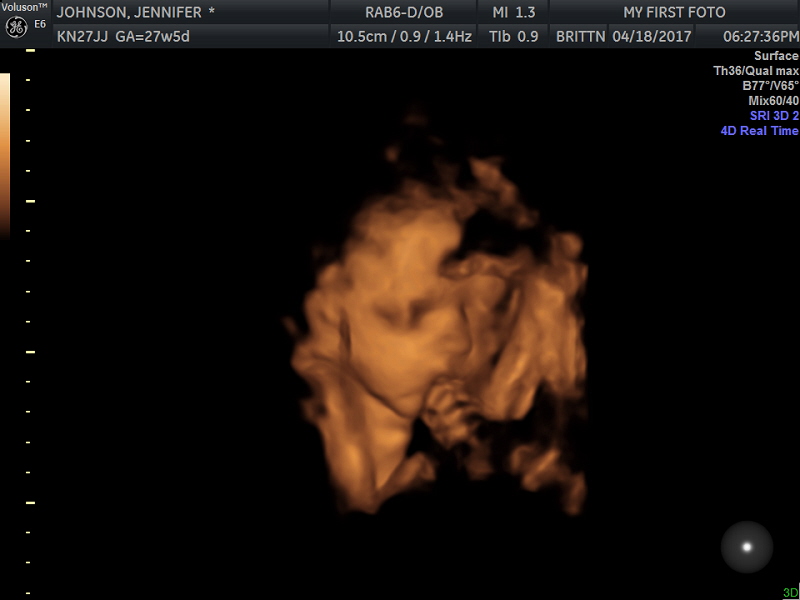

Everything thus far has been going textbook perfect, really. I’m gaining weight as I should be, there’s no protein in my urine (which they use as a warning sign for pre-eclampsia), and he is just moving up a storm in there. Our Little Bear is a mover and a shaker, that’s for sure. We aren’t sure what his estimated weight will be at this point, but Dean and I both were chubby little babies so we will see what this little man does. What I do know is that he prefers his foot to be in his face, and thus my rib-cage almost all the time – and now I have photographic proof! I just realized typing this that I never posted the pictures of his 3D ultrasound appointment here! I am going to post these in their full size, for easy viewing. As this was ~6 weeks ago, I’m sure he’s put on some weight and is looking even cuter. I’m completely obsessed with his hands, toes, and cheeks. If you ever needed additional proof (you know, besides IVF in general) that science and technology are amazing – just look at these images. This is no 2D ultrasound where you can ‘sort of’ make out the features, this is all right there in front of you! Dean and I have become experts at spotting things via ultrasound in the last year and a half, but not everyone is as versed as we are.

Here he is (click the images for a bigger size):